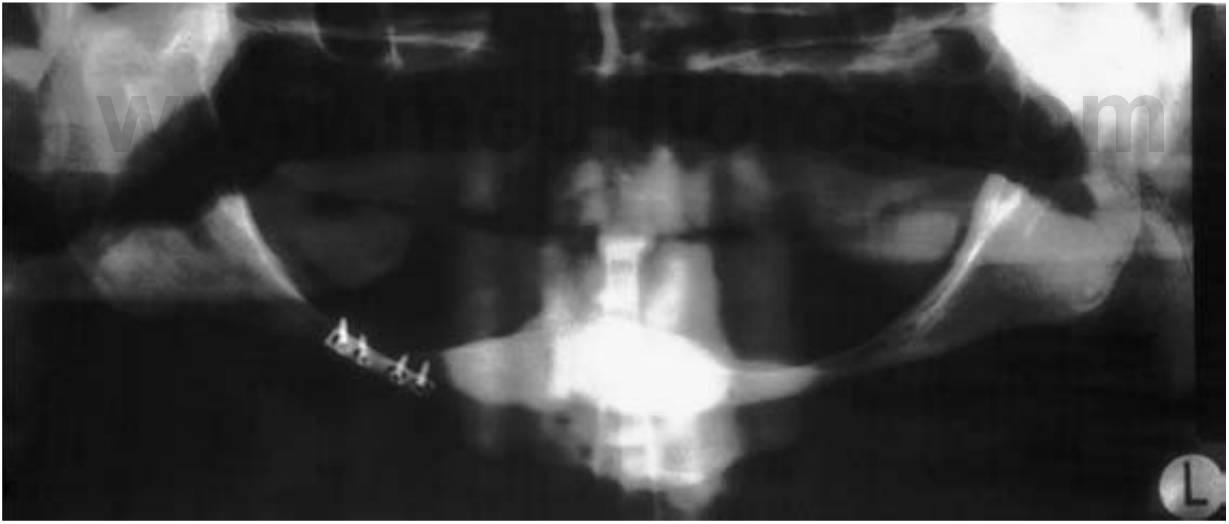

La pérdida de hueso en el maxilar o la mandíbula no se limita a hueso alveolar; también pueden ser reabsorbidas algunas porciones de hueso basal (fig. 1-18), especialmente en el aspecto posterior de la mandíbula donde una reabsorción grave puede producir una pérdida ósea de hasta el 80%. El contenido del canal mandibular o del foramen mentoniano puede volverse eventualmente dehiscente y servir como parte del área de soporte de la prótesis. como resultado se pueden producir dolor agudo y parestesia transitoria o permanente en las áreas inervadas por el nervio mandibular. Existe también un aumento del riesgo de frac tura del cuerpo mandibular, incluso bajo el efecto de impactos de muy baja intensidad (fig. 1-19). La fractura mandibular hace que esta se desplace hacia un lado y provoca que su estabilización y el resultado estético obtenido durante el tratamiento sea más difícil de obtener.